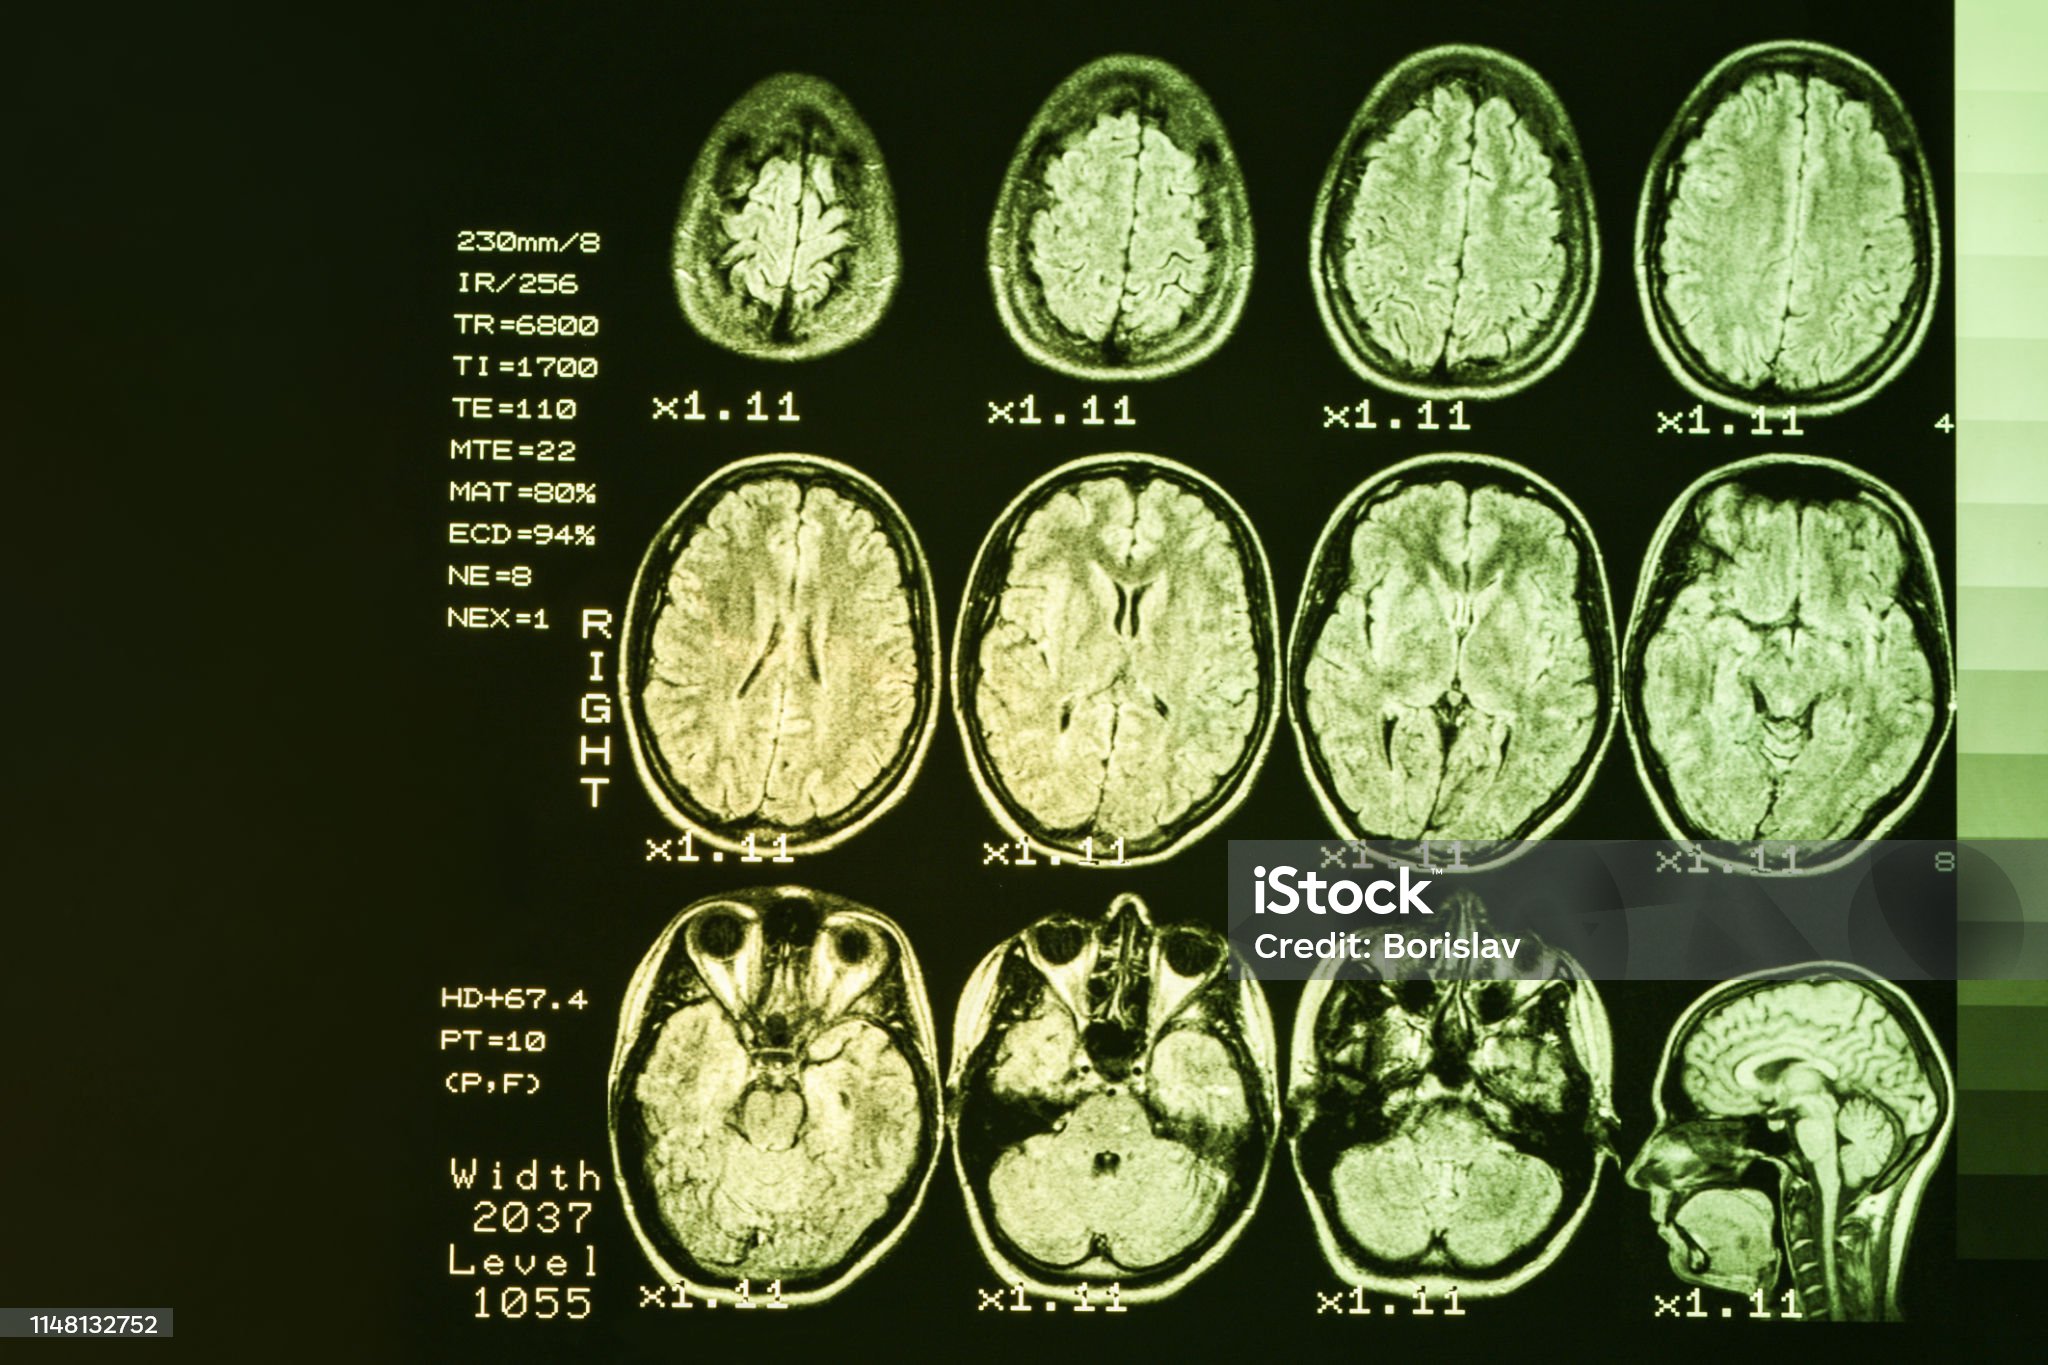

2-2 뇌의 변화: 헌팅턴병은 주로 선조체(striatum)와 대뇌피질에서 신경세포의 퇴행을 초래하며, 이는 인지 기능과 운동 조절에 영향을 미칩니다. 반면, 알츠하이머병에서는 해마(hippocampus)와 관련된 기억 기능의 손상이 주된 특징입니다.

헌팅턴병과 알츠하이머병은 모두 신경퇴행성 질환이지만, 원인과 진행 과정에서 차이가 있습니다. 헌팅턴병은 HTT 유전자의 CAG 반복 확장으로 인해 발생하며, 주된 뇌 손상 부위는 선조체와 대뇌피질입니다. 반면, 알츠하이머병은 베타 아밀로이드 단백질의 침착과 타우 단백질의 이상이 주요 원인으로 작용하며, 주로 해마와 대뇌피질이 손상됩니다.